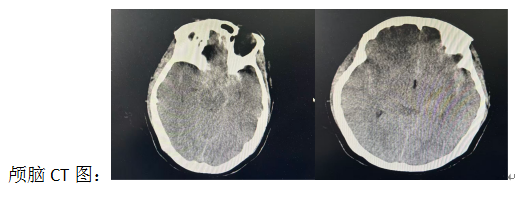

科室李琦医生接诊后,为高女士完善头颅CT,结果显示:蛛网膜下腔出血。情况危急,卒中绿色通道立即启动。此时高女士已经神志昏迷,血压156/89毫米汞柱,双侧瞳孔直径2.0毫米,四肢肌力无法评估,颈抵抗阳性。Hunt-Hess分级:III级;改良Fisher分级:3级;mRS评分发病前:0分,发病后5分;GCS评分:9分。颅脑CTA提示:左侧颈内动脉C6、C7段交界区见一囊带状突起,大小约14毫米x10毫米。诊断为脑动脉瘤破裂伴蛛网膜下腔出血、继发癫痫。

当晚8时15分,高女士被送入介入室,行脑血管造影示:左侧经内动脉C6段囊性动脉瘤(长x宽x颈:15毫米x10.9毫米x5.3毫米);动脉瘤破裂出血,有进一步介入治疗指征。再次告知患者及家属介入治疗的必要性及风险后,患者及家属表示知晓并签署手术同意书。随即手术团队为高女士在全麻下行颅内动脉瘤支架辅助弹簧圈栓塞术:从建立通路到达血管-微导管置于瘤腔-再到支架释放+弹簧圈栓塞-栓塞完毕一气呵成,4个半小时后手术顺利结束,术中患者生命体征平稳。术后复查颅脑CT,颅内出血较前只有稍增多。11月8日复查颅脑CT出血无增多,患者也未出现神经功能缺损表现;11月10日再次复查颅脑CT对比术后颅脑CT片子时,颅内高密度影较前也减少。